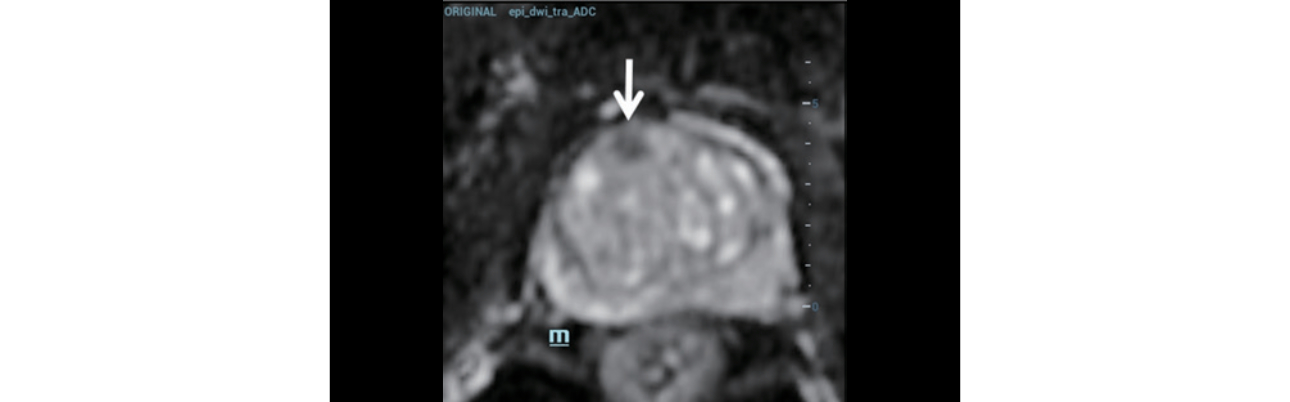

Multi-parameter MRI ??:?

- ??? ?? ??? ?? ?? (PI-RADS classification 4).

- ??? ??? ???? ??? ??? ???.

TRUS ?? (figure 1):?

- ??? ??? ???? ??? ??? ???.

- ? ??? ???? ?? ??(heterogeneous) ??? echotexture.